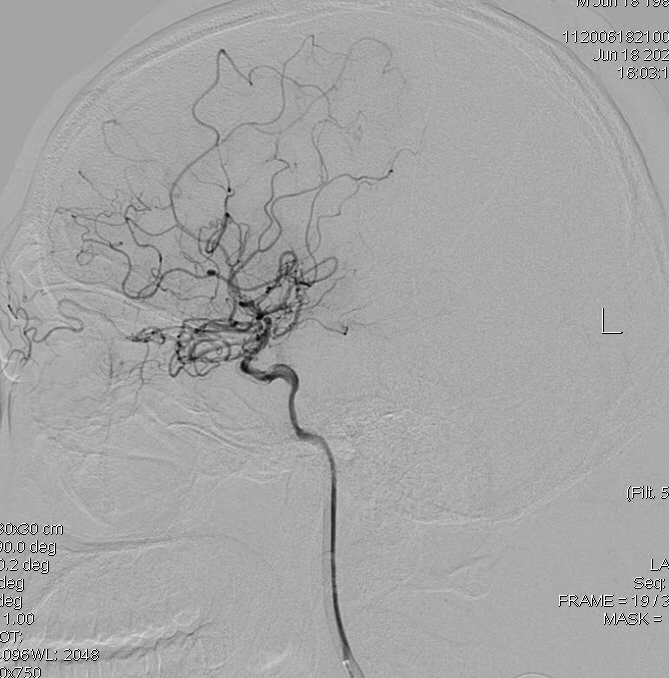

造影显示右侧大脑前明显变细,大脑中只有很少的分支:

左侧大脑中分支更少,虽然正位看还有一些分支,但是侧位看,大脑半球上外侧面大面积的区域没有血液供应,尤其功能区: